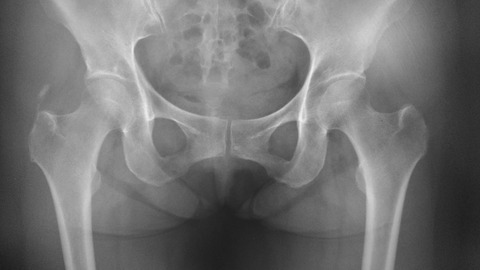

右大腿骨大転子部のやや中枢側に線状の石灰沈着を認めます。いわゆる石灰沈着性中殿筋腱炎ですね。以前にMRIで発見した症例はありましたが、単純X線像では初めてです。